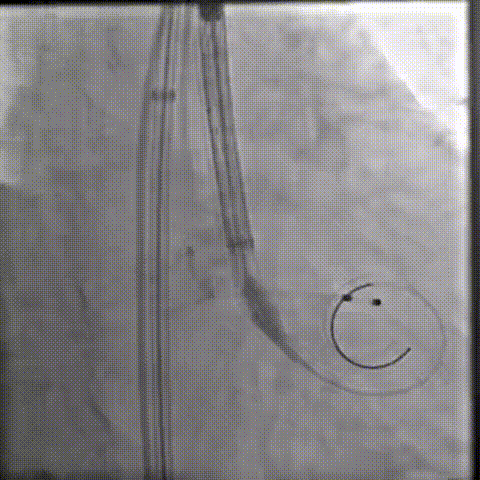

20球囊预扩

器械过弓柔顺

初始定位